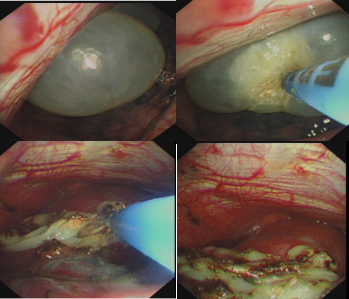

据冯起校主任介绍,与VATS相比,内科胸腔镜采用局部麻醉(或加用静脉镇静)下胸壁单一微小切口来完成操作,在内镜室即可完成,不需要全麻单肺机械通气,对患者生命体征的干扰较小,而且花费不到VATS的十分之一,具有更安全、更经济、更有效的特点。“以邓伯为例,采用内科胸腔镜下氩气刀肺大疱治疗术,可见肺大疱逐渐萎缩凝固成为焦痂,后置入胸腔引流管,术后当天引流瓶内即无气泡冒出,肺完全复张,手术操作过程不到20分钟,发现肺大疱后在数分钟即可完成肺大疱处理,整个操作过程病人的各项监测指标稳定,疗效较外科手术有过之而无不及”冯起校主任说到。

内科胸腔镜下氩气刀治疗肺大疱:

据了解,南方医科大学中西医结合医院呼吸科/胸部肿瘤内科是中国医师协会呼吸内镜医师培训基地,在呼吸介入的治疗方面已经拿了三个全国第一。冯起校专家团队从2017年底开始利用内科胸腔镜治疗肺大疱和难治性自发性气胸积累了丰富的经验,运用内科胸腔镜下氩气等离子体凝固技术(APC,又称氩气刀)治疗胸膜下可见肺大疱取得十分良好的效果,半年多来已治疗近20例次患者均一次性成功,无严重并发症出现,院后随访均无异常。APC是一种应用高频电流将氩气电离,以非接触方式达到组织凝固的方法,氩气刀引起的凝固更为表浅,组织穿透较浅,安全性较高,而且表浅烧灼后有助于促进肺大疱的瘢痕修复,减少复发。